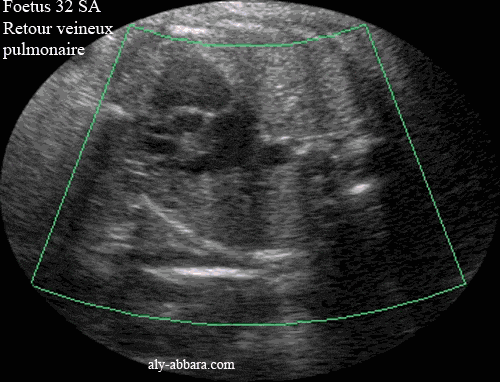

Image échographique (avec Dynamic Flow) montrant le retour veineux pulmonaire qui se fait par l'intermédiaire des quatre veines pulmonaires (deux venant de la circulation veineuse pulmonaire droite et celle du poumon gauche) ; ces quatre veines acheminent le sang veineux à l'oreillette gauche du cœur

Fœtus de 32 semaines d'aménorrhée